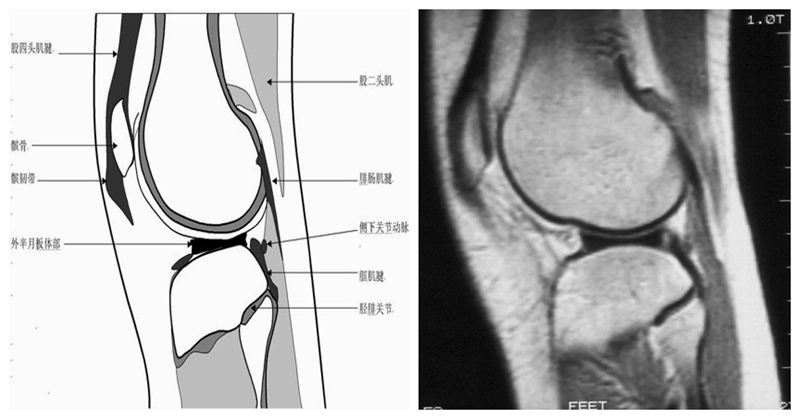

膝关节矢状面正常解剖MRI表现

可整段显像髌韧带、前后交叉、外侧韧副带结构,侧重的股胫软骨中部和半月板前后角,通常是诊断半月板撕裂或变性最为关键的断面。